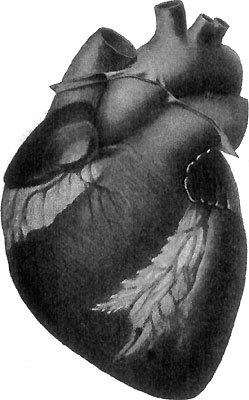

116 The Exterior of the Heart